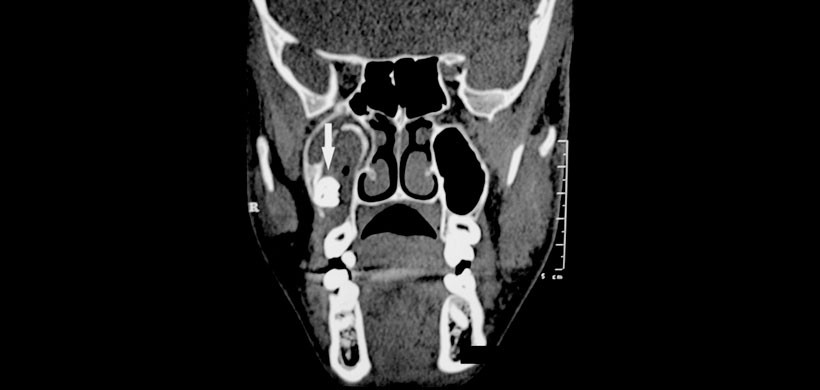

Se optó primero por realizarle una radiografía panorámica la cual muestra una radiolucides  que involucra el seno maxilar derecho junto con el tercer molar impactado (figura 1). Posteriormente se realizó una radiografía de senos paranasales para determinar que la piezas 18 este dentro del seno maxilar derecho (Figura 2) y finalmente se pudo comprobar mediante la tomografía computarizada y a su vez determinar el tamaño de la lesión así como las estructuras óseas y dentarias afectadas. (Figura 3)

Para concluir podemos mencionar que si bien las imágenes 2D sirven de mucha ayuda en la detección de lesiones, las imágenes en 3D son la herramienta de elección para determinar la localización de la lesión así como su repercusión en las estructuras adyacentes.